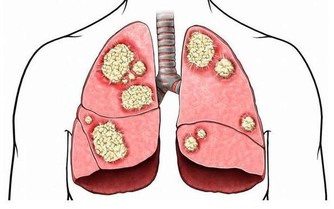

另據研究表明,豆角能顯著降低血清膽固醇的含量,有利於高血壓患者的康復,可作為高血壓患者的保健蔬菜。豆角中還含有效成分能抑制癌細胞的生長,豐富的粗纖維能促進大便的排泄,因此可作為防治腸道癌瘤的食品。